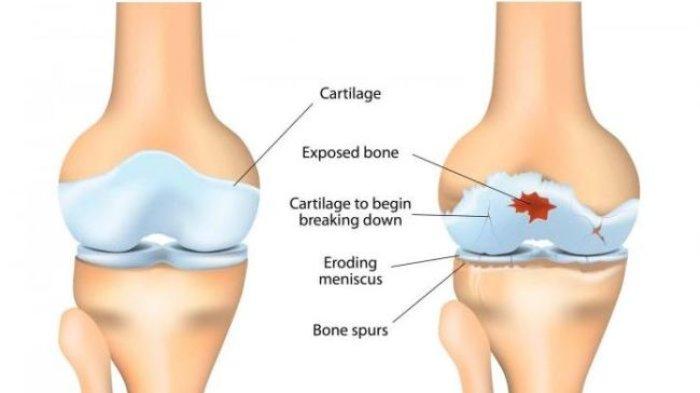

Osteoarthritis (OA) adalah penyakit degeneratif akibat kerusakan pada kartilago sendi, peradangan, dan pembentukan tulang baru di sekitar sendi. Hal ini dapat menyebabkan nyeri, kekakuan, hingga terbatasnya fungsi sendi.

PRP adalah plasma darah yang mengandung konsentrasi trombosit yang lebih tinggi dari plasma normal. Trombosit mengandung faktor pertumbuhan, protein, dan sitokin yang berperan dalam proses penyembuhan jaringan. Saat dokter menyuntikkan plasma ke dalam sendi yang terkena osteoarthritis, faktor-faktor pertumbuhan dalam trombosit akan merangsang proses perbaikan dan regenerasi jaringan. Mereka mendorong proliferasi sel-sel kondrosit dan matriks ekstraseluler, meningkatkan sintesis kolagen, dan mengurangi peradangan.

- Memperbaiki kartilago: Faktor pertumbuhan dalam PRP dapat merangsang regenerasi dan perbaikan kartilago yang rusak.

- Mengurangi peradangan: Komponen antiinflamasi dalam PRP dapat membantu mengurangi peradangan dan mencegah kerusakan lebih lanjut pada sendi.